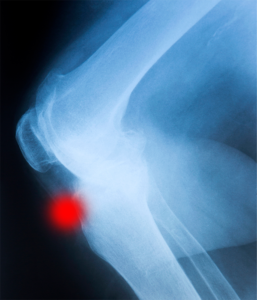

La enfermedad de Osgood Schlatter es una inflamación que afecta la tuberosidad tibial anterior, justo por debajo de la rodilla. Es una de las patologías más comunes en adolescentes activos, especialmente aquellos que practican deportes como fútbol, baloncesto o atletismo. Esta protuberancia se denomina espina tibial anterior.

En muchos casos, el dolor puede aparecer durante el ejercicio y aliviarse con el reposo, pero en fases avanzadas puede mantenerse constante. En Podoactiva, realizamos un diagnóstico clínico y biomecánico completo. Además de una exploración física, se puede recurrir a pruebas de imagen como radiografías o ecografías para confirmar el grado de afectación ósea o inflamatoria, ya que se puede apreciar la inflamación o daño en la espina tibial.